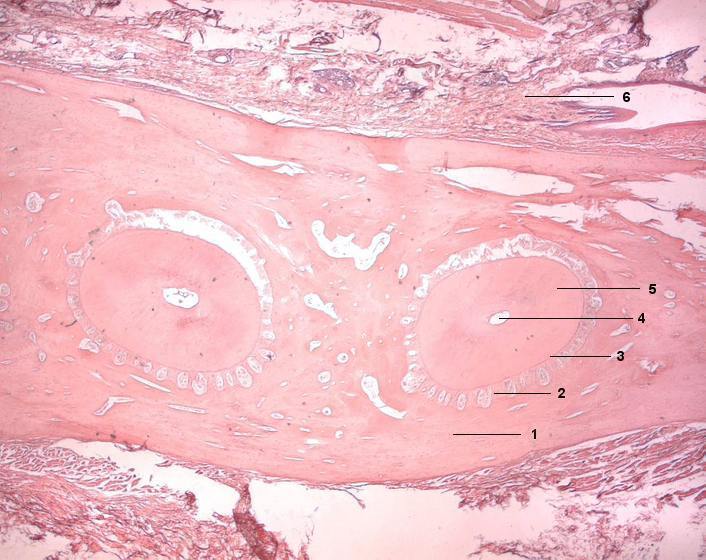

1 Alveolarknochen

2 Periodontium (Wurzelhaut)

3 Zement

4 Pulpahöhle

5 Dentin

6 Bindegewebe der Gingiva